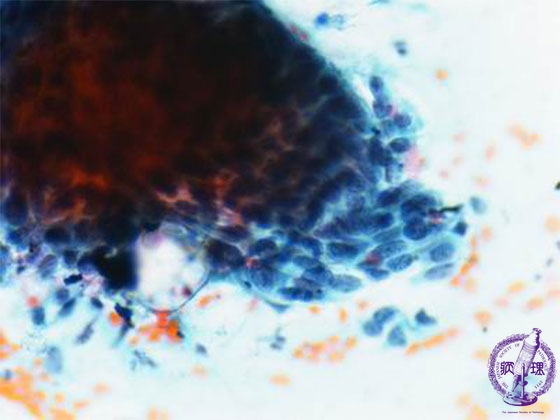

• (2)Vaginal smear cytology(non-keratizing type squamous cell carcinoma)

Non-keratinizing squamous cell carcinoma The background was bloody and necrotic.The cancer cells appeared singly and in large sheets. The nuclei are enlarged and have dense chromatin.